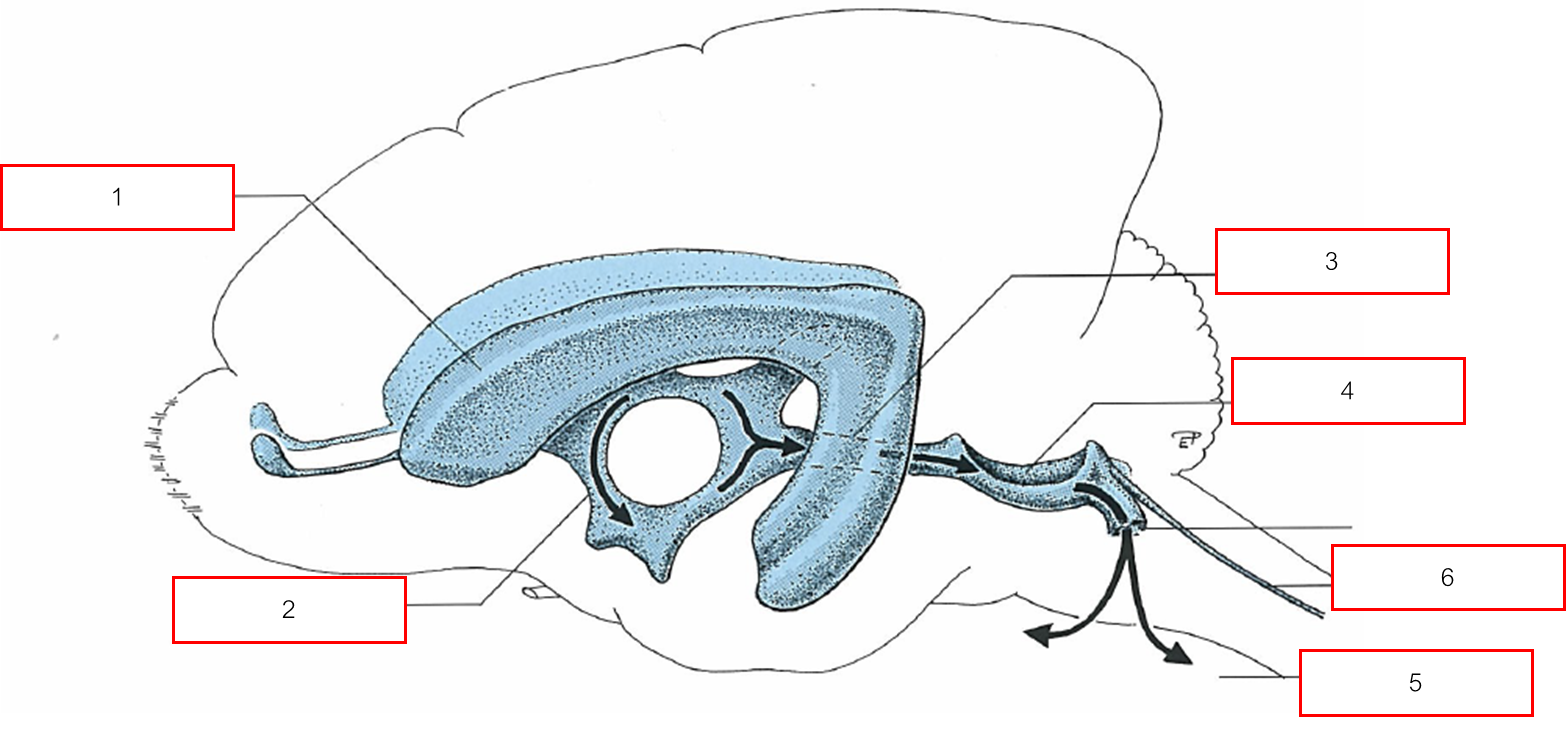

VENTRICULAR SYSTEM

Lateral ventricle

Third ventricle

Mesencephalic aqueduct

Fourth ventricle

Subarachnoid space (เปิดที่ Lateral recess)

Central canal